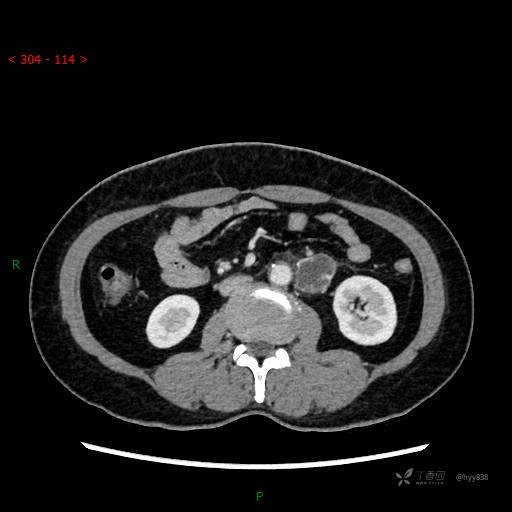

静脉期

CT平扫是外院的,因图像质量原因,不方便上传!